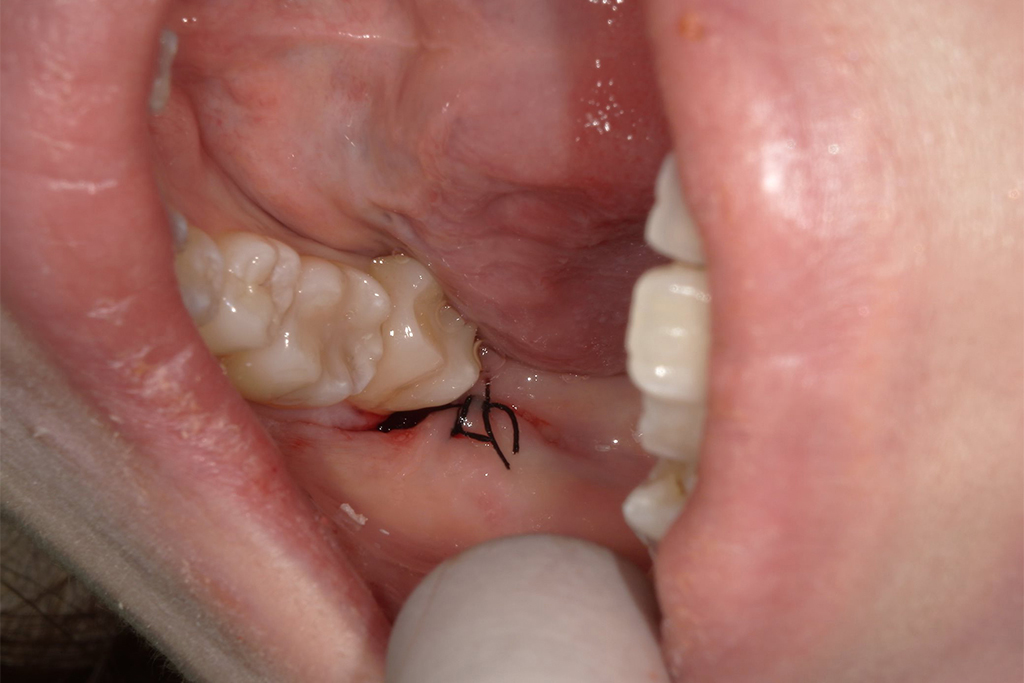

| 患者の年齢 | 30歳 |

|---|---|

| 症状 | 親知らずが痛い。横向きに生えている |

| 治療内容 | 親知らず抜歯1本 |

| 費用 | 約8,500円 (検査料、CT費、処置料、処方箋費用) |

| 治療期間 | 1日 |

| デメリット・ リスク |

麻痺が起こる場合がある、痛みが伴う |